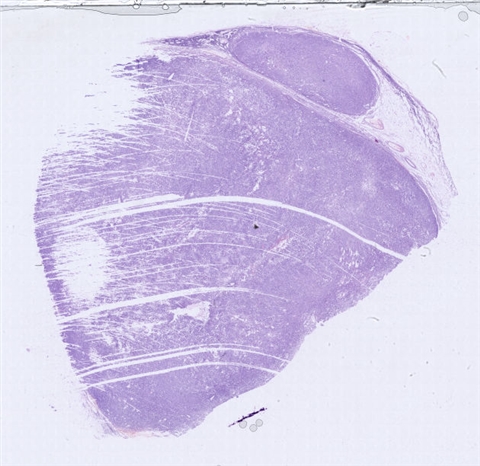

案例2 (6860)

性别:       年龄:73

患者详情: 于手术前10天无意中发现左侧大腿内侧肿物,体检肿物位于皮下,病程不详,无其他有关症状,入院后其他检查无特殊,在全麻下行肿物切除,术中肿物位于皮下

大体所见: 肿物大小3.5*3*2.5厘米

医院: 上海交通大学医学院附属新华医院崇明分院